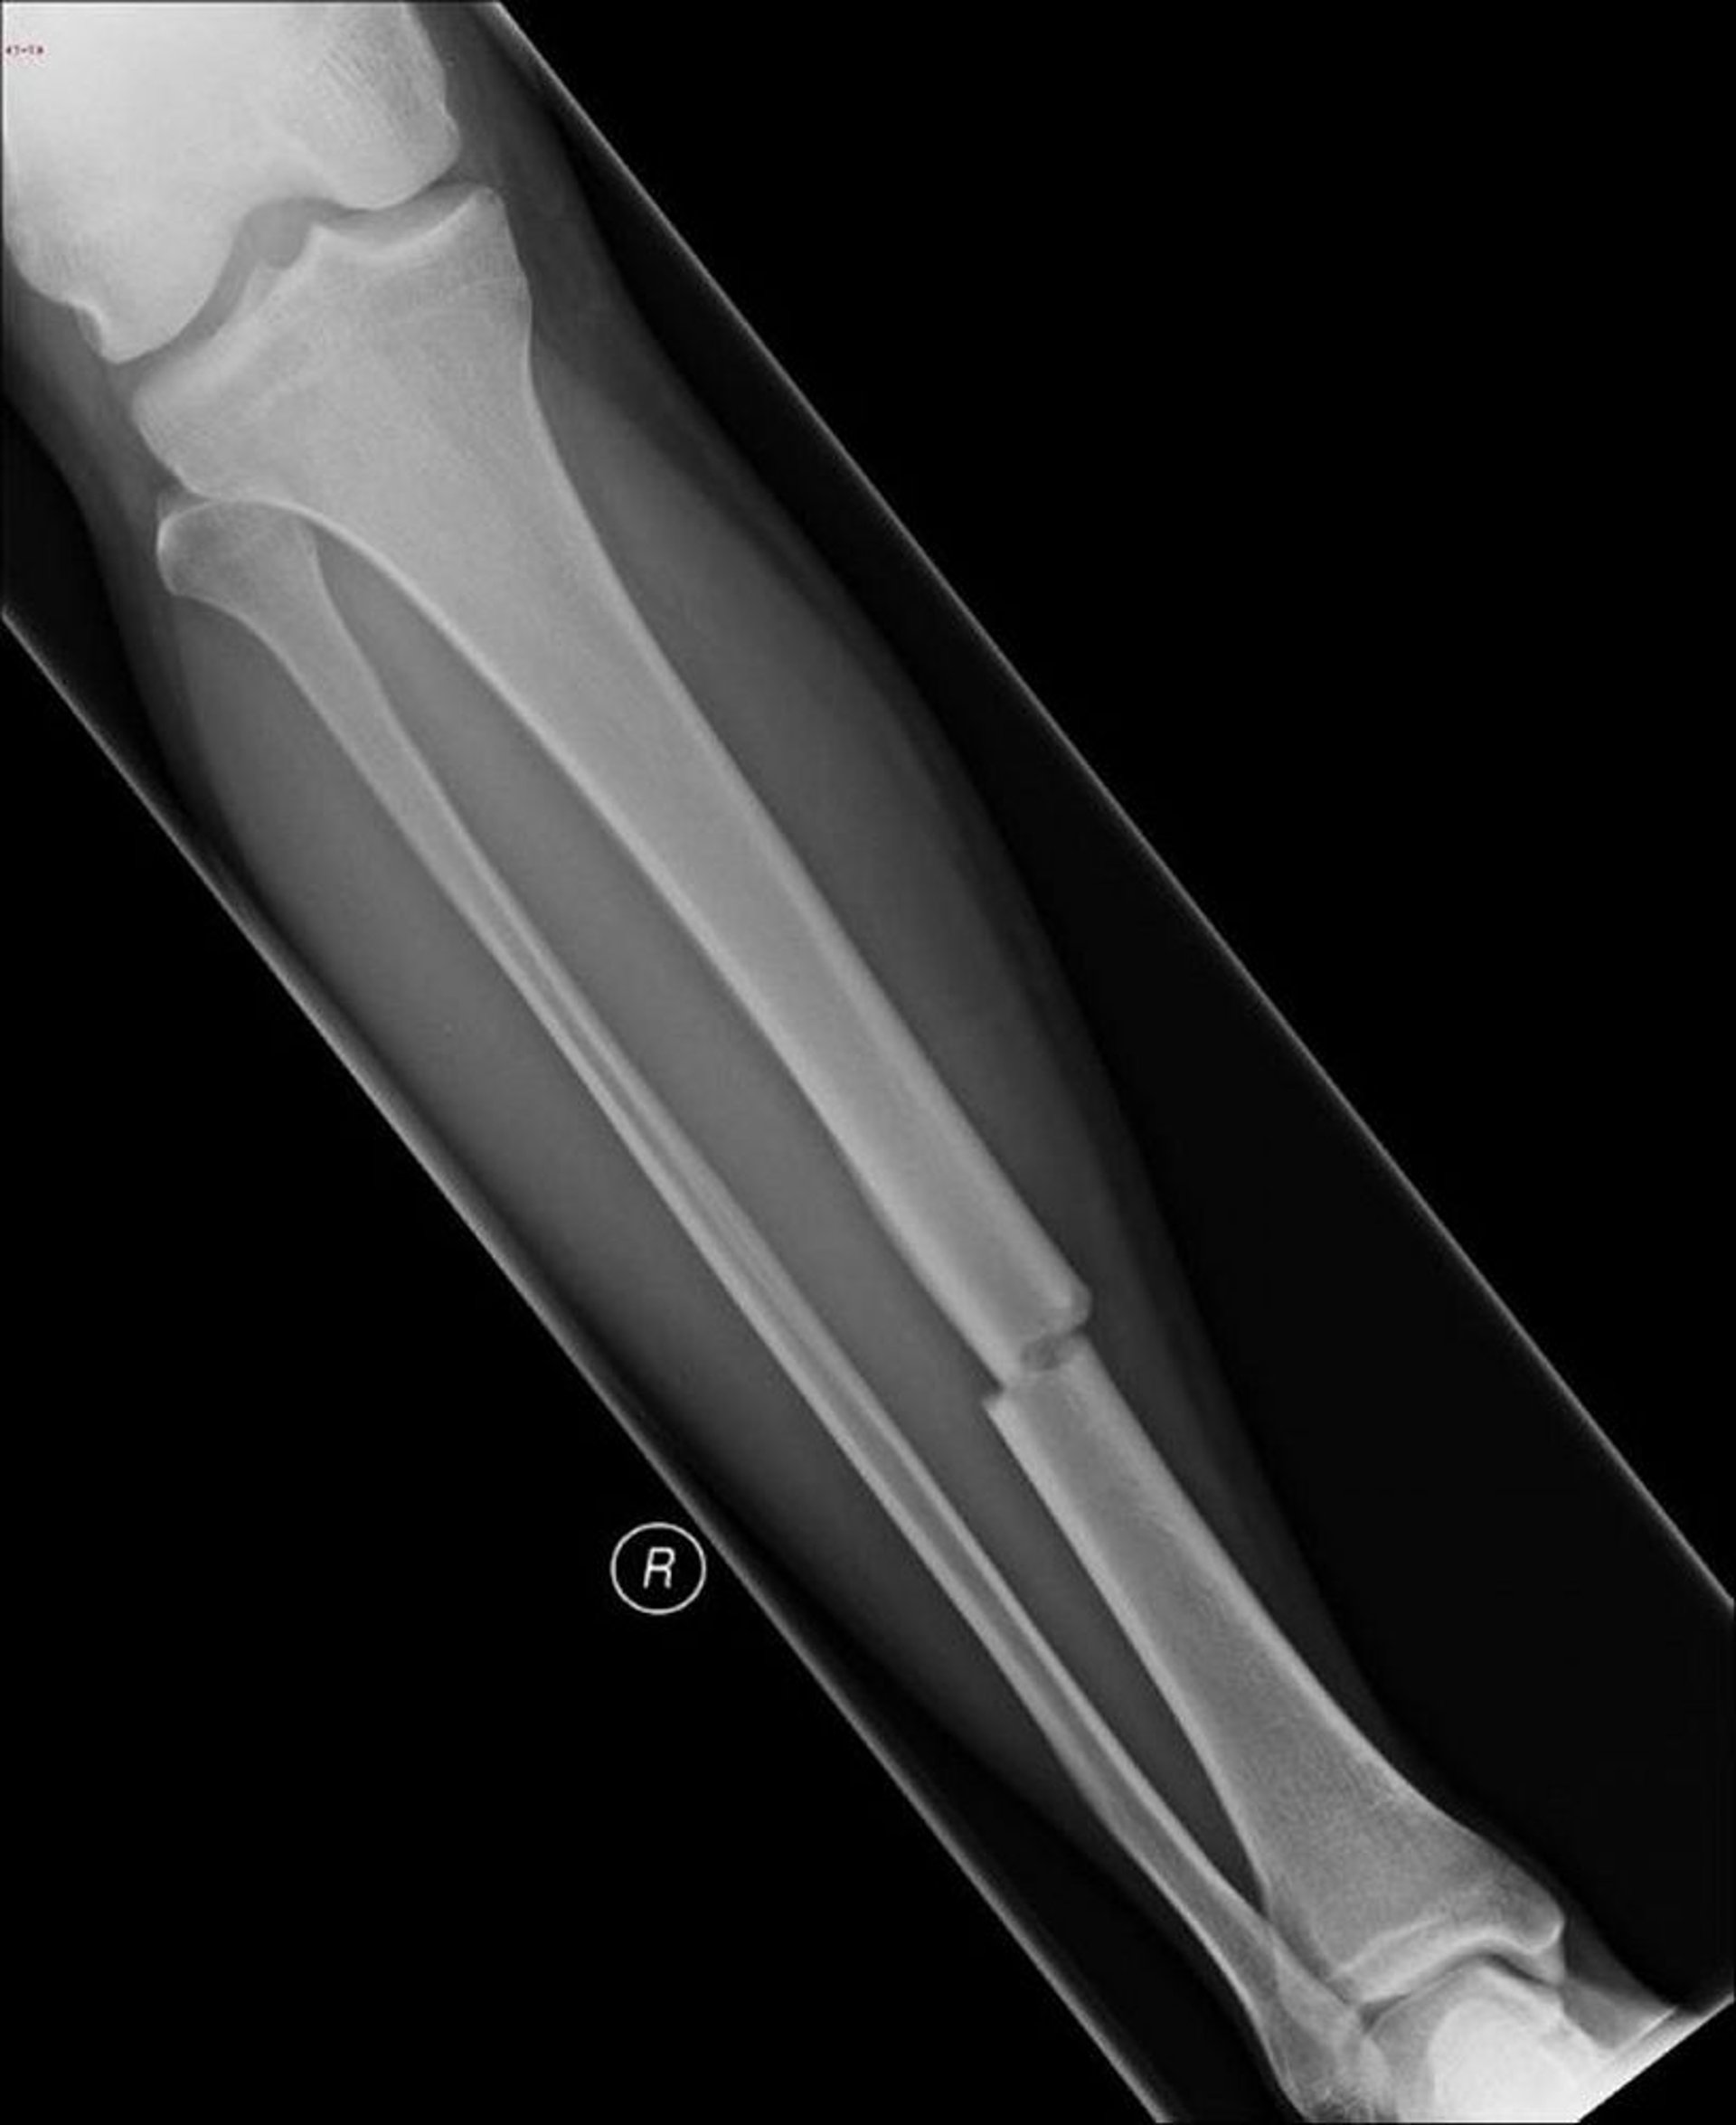

Questa radiografia mostra una frattura nella parte centrale della tibia.

Immagine per gentile concessione della dottoressa Danielle Campagne.